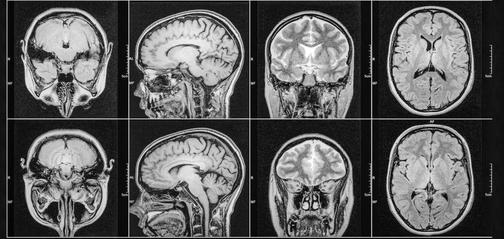

Затемнение на мрт

Затемнение на мрт 140 фото